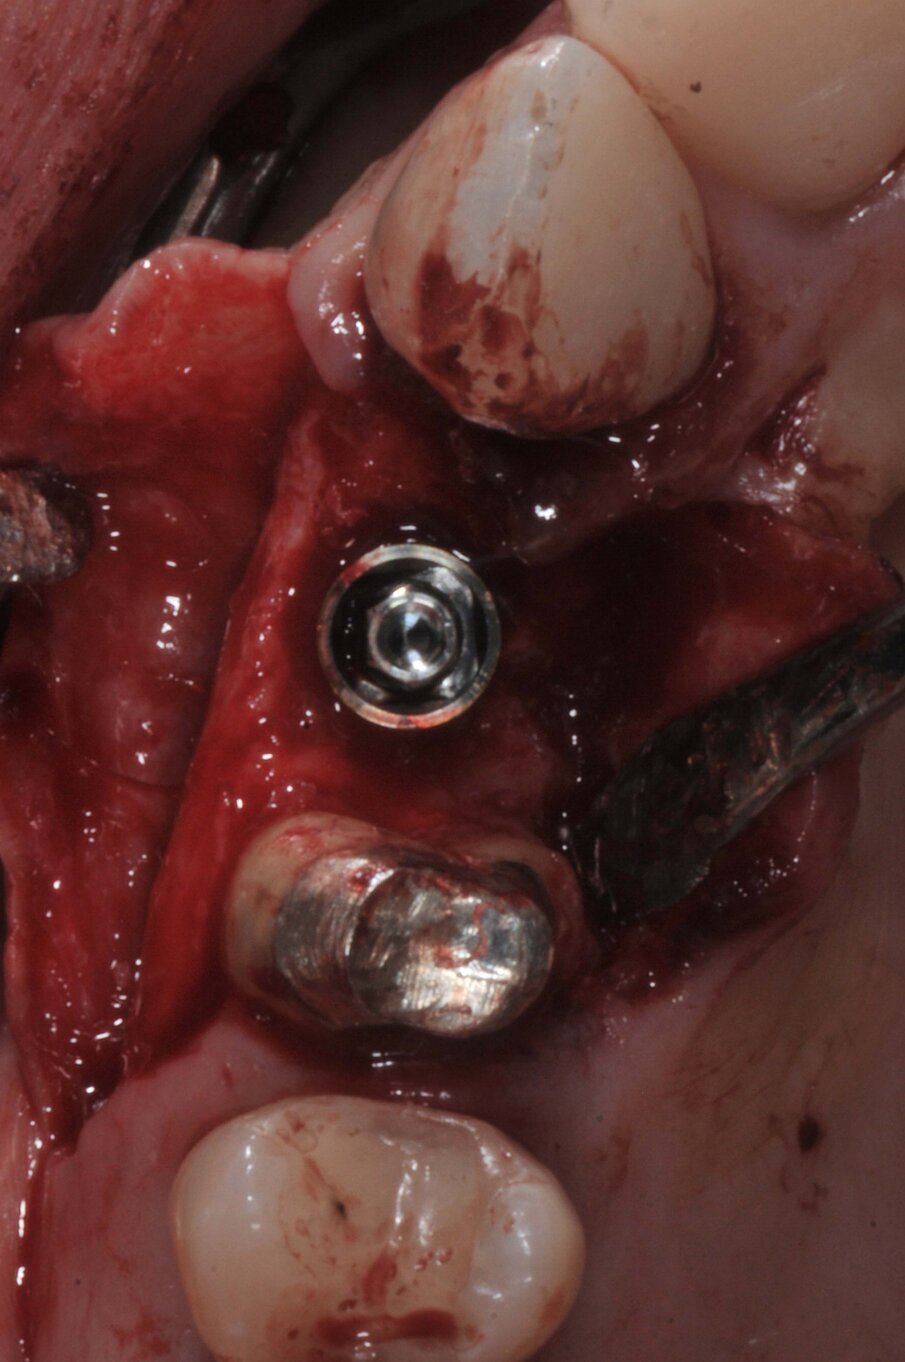

Le corone sui denti 1.3 e 1.4 furono rimosse, il dente 1.3 fu estratto e l’alveolo fu riempito con una membrana di PRGF ottenuta tramite centrifugazione del sangue della paziente con il sistema Endoret e un provvisorio fu consegnato sui denti 1.3 e 1.4 (Fig. 5, 6). Dopo otto settimane fu eseguita una nuova cone-beam e la chirurgia fu pianificata (Fig. 7). Si eseguì un lembo a tutto spessore, fu eseguita l’osteotomia e fu inserito un impianto BTI Core 3.5 × 8.5. Un pilastro Unit fu avvitato e un tappo di guarigione fu applicato. L’osso ottenuto dalla fresatura mescolato con una membrana di PRGF fu applicato sul lato palatale per compensare una piccola deiscenza, una seconda membrana fu applicata sopra l’osso circostante e un innesto di tessuto connettivo prelevato dalla tuberosità fu suturato vestibolarmente per ricreare la bozza canina. Punti di sutura staccati furono eseguiti con un filo in PTFE (Figg. 8-11). Dopo quattro mesi il provvisorio fu rimosso e i tessuti apparivano sani e con un buon spessore di tessuto connettivo vestibolare per garantire la stabilità nel tempo del risultato. Fu eseguita un’impronta con la tecnica del cucchiaio aperto e dopo due settimane furono consegnate una corona in zirconio cementata sul dente 14 ed una avvitata sul denta 1.3. Il profilo di emergenza della corona sull’impianto appariva ideale. Purtroppo, a causa della mancanza del picco osseo sul versante distale del dente 1.2, non si ottenne una papilla di altezza adeguata. Ciononostante la paziente si disse soddisfatta del risultato e rifiutò ulteriori terapie per correggere il difetto residuo (Figg. 12-15).